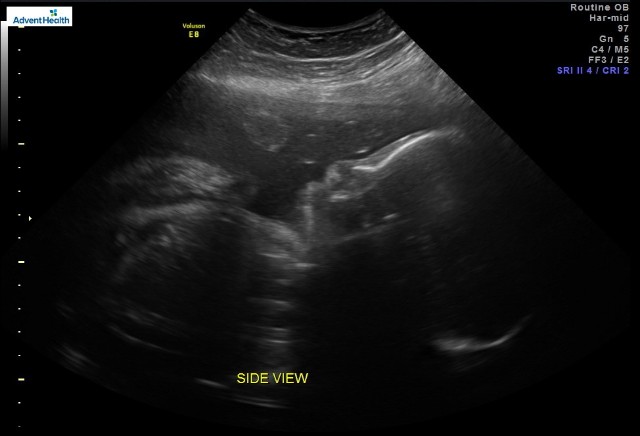

Baby Rowan will be making his appearance on February 11th !!!

My.nerves are shot lol 3 and half weeks . Its gonna be different with 2 kids a girl and now a boy